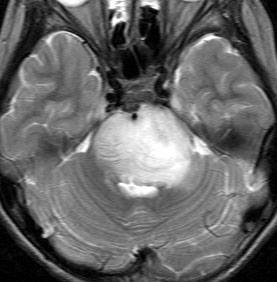

MRI画像診断

- MRIでは脳幹部(とくに橋)が腫れて大きくなります

- 多くの場合は左右対称ですが,非対称のものもめずらしくありません

- MRIのFLAIR(フレア)画像とかT2強調画像で,白くぼーっと滲んだように映ります

- 脳幹部の橋というところを中心にして発生し,上方の中脳や下方の延髄に浸潤して伸びていきます

- 腫瘍は大きいのですが,水頭症にならないのが特徴です(水頭症は2割くらい)

- 上の写真の例では,症状は軽く,たいていの場合はこのくらいの大きさになってから発見されます

- 腫瘍の前方の中心に黒い点のようなものが見えますが,これは脳底動脈で,この脳底動脈の囲い込み engulfment は,DIPGに特徴的なものといえます

- 腫瘍の一部分だけが脳幹部から突出してキノコのように伸びる所見 exophytic grwoth は2割くらいにみられます

- 腫瘍内部に小さな腫瘍内出血が生じることもあります